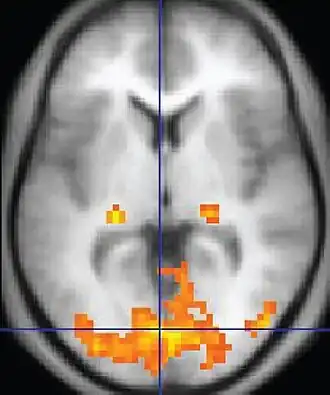

| Functional MRI (fMRI) | Blood-oxygen-level dependent imaging | BOLD | Changes in oxygen saturation-dependent magnetism of hemoglobin reflects tissue activity.[29] | Localizing brain activity from performing an assigned task (e.g. talking, moving fingers) before surgery, also used in research of cognition.[30] |

|

Functional MRI

Functional MRI (fMRI) measures signal changes in the brain that are due to changing neural activity. It is used to understand how different parts of the brain respond to external stimuli or passive activity in a resting state, and has applications in behavioral and cognitive research, and in planning neurosurgery of eloquent brain areas.[48][49] Researchers use statistical methods to construct a 3-D parametric map of the brain indicating the regions of the cortex that demonstrate a significant change in activity in response to the task. Compared to anatomical T1W imaging, the brain is scanned at lower spatial resolution but at a higher temporal resolution (typically once every 2–3 seconds). Increases in neural activity cause changes in the MR signal via T*

2 changes;[50] this mechanism is referred to as the BOLD (blood-oxygen-level dependent) effect. Increased neural activity causes an increased demand for oxygen, and the vascular system actually overcompensates for this, increasing the amount of oxygenated hemoglobin relative to deoxygenated hemoglobin. Because deoxygenated hemoglobin attenuates the MR signal, the vascular response leads to a signal increase that is related to the neural activity. The precise nature of the relationship between neural activity and the BOLD signal is a subject of current research. The BOLD effect also allows for the generation of high resolution 3D maps of the venous vasculature within neural tissue.